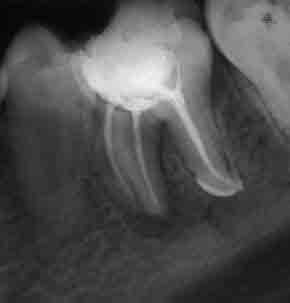

Запълване с препресване

Ендодонтия